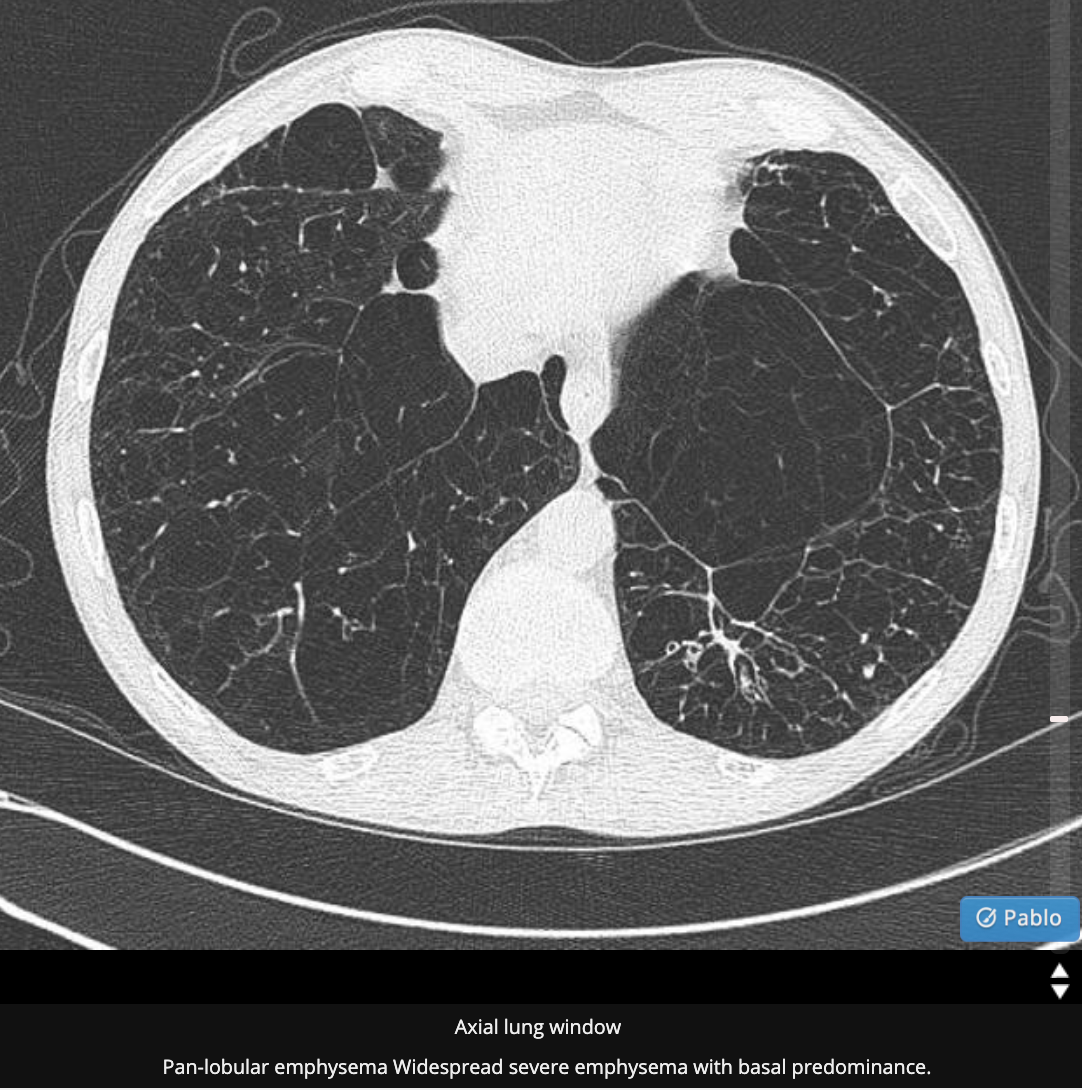

patterns of emphysema

Emphysema

Intro cause